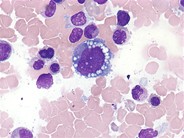

Anaplastic Large Cell Lymphoma ALK+ H&E

Category: Lymphoma: Mature T and NK cell lymphoproliferations > Mature T-cell Lymphomas > Anaplastic Large Cell Lymphoma, ALK positive

See reference case "Anaplastic Large Cell Lymphoma" for details.